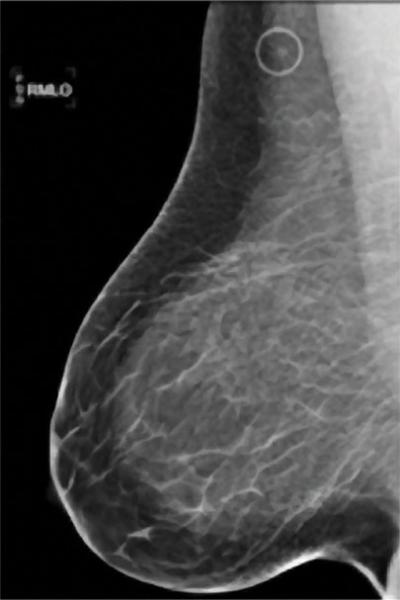

A comparision of a small breast cancer found in a patient without dense breast tissue (left), and a tumor found in a woman with dense fibroglandular tissue. For more information visit DenseBreast-info.org.

Roughly 40 percent of women of mammographic age (40 and older) fall into the last two categories, which are collectively considered dense. As density increases, it becomes more difficult to distinguish tumors and other masses from the surrounding tissue. Apart from this masking effect, dense breast tissue is itself a risk factor for developing breast cancer. Statistical evidence indicates that women with dense breasts are four to six times more likely to develop breast cancer than women with fatty tissue; they are also 17 times more likely to develop interval cancer (detected or presenting less than 12 months following a normal mammogram).